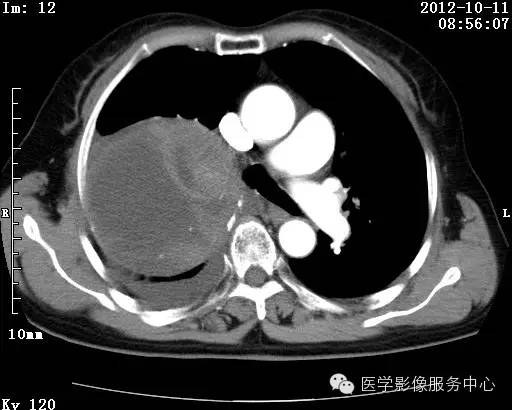

【病例】右肺巨大错构瘤1例CT影像表现

病史:女 65岁咳嗽咳痰 右肺巨大肿块就诊。

错构瘤的主要组织成分包括软骨、脂肪、平滑肌、腺体、上皮细胞,有时还有骨组织或钙化。错构瘤一般为实质致密的球形、卵圆形,也可以是分叶状或结节状,大多数直径在3cm以下。

错构瘤的发病年龄多数在40岁以上,男性多于女性。 绝大多数错构瘤(约80%以上)生长在肺的周边部,紧贴于肺的脏层胸膜之下,有时突出于肺表面。其特征钙化为爆米花样钙化,内有脂肪软骨成分等等。最常见的部位是胸膜下肺实质内,其次为主支气管或肺叶、肺段支气管内。

瘤内出现“爆米花样钙化”是诊断的主要指标之一。早期的点状、斑片状及结节状钙化 随时间增加钙化数量及范围会增加,最终可能演变 为爆米花样钙化;

另一项主要指标是瘤测得脂肪成分是诊断错构瘤。